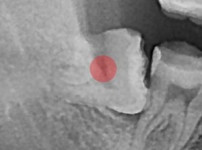

완전 매복 사랑니

조회

949

작성일

25-11-28